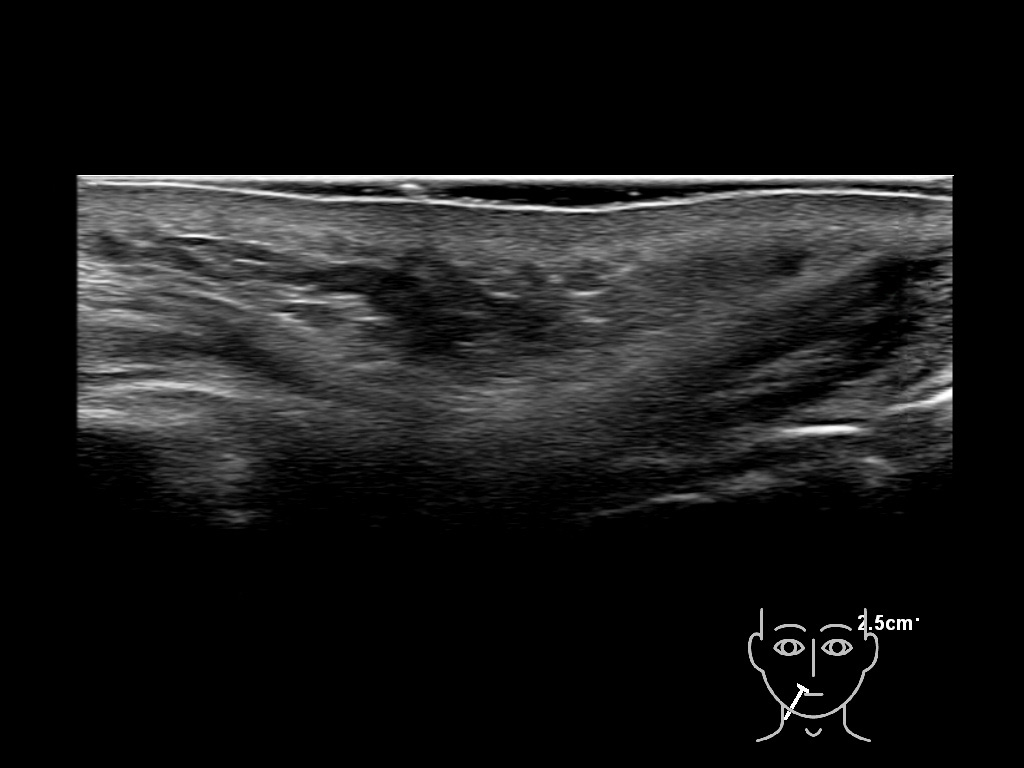

With ultrasound signs of inflammation can be visualized. Edema can be seen as a hyperechoic appearance of the subcutaneous fat, sometimes separated by hypoechoic fluid filled area’s, known as cobblestone appearance. Increased vascularization (hypervascularity) can be seen on colour Doppler. An abscess will appear as a fluid collection appearing as an irregular hypoechoic area with heterogeneous internal echoes and a thickened wall. Posterior acoustic enhancement can be present, and there is vascularity around but not within the mass. Under ultrasound guidance, abscesses can be managed by needle aspirations (18G) under antibiotic cover.

Study the first image to recognize the different layers. If you are sure about the layers, swipe to the second image to view the answer (if applicable).